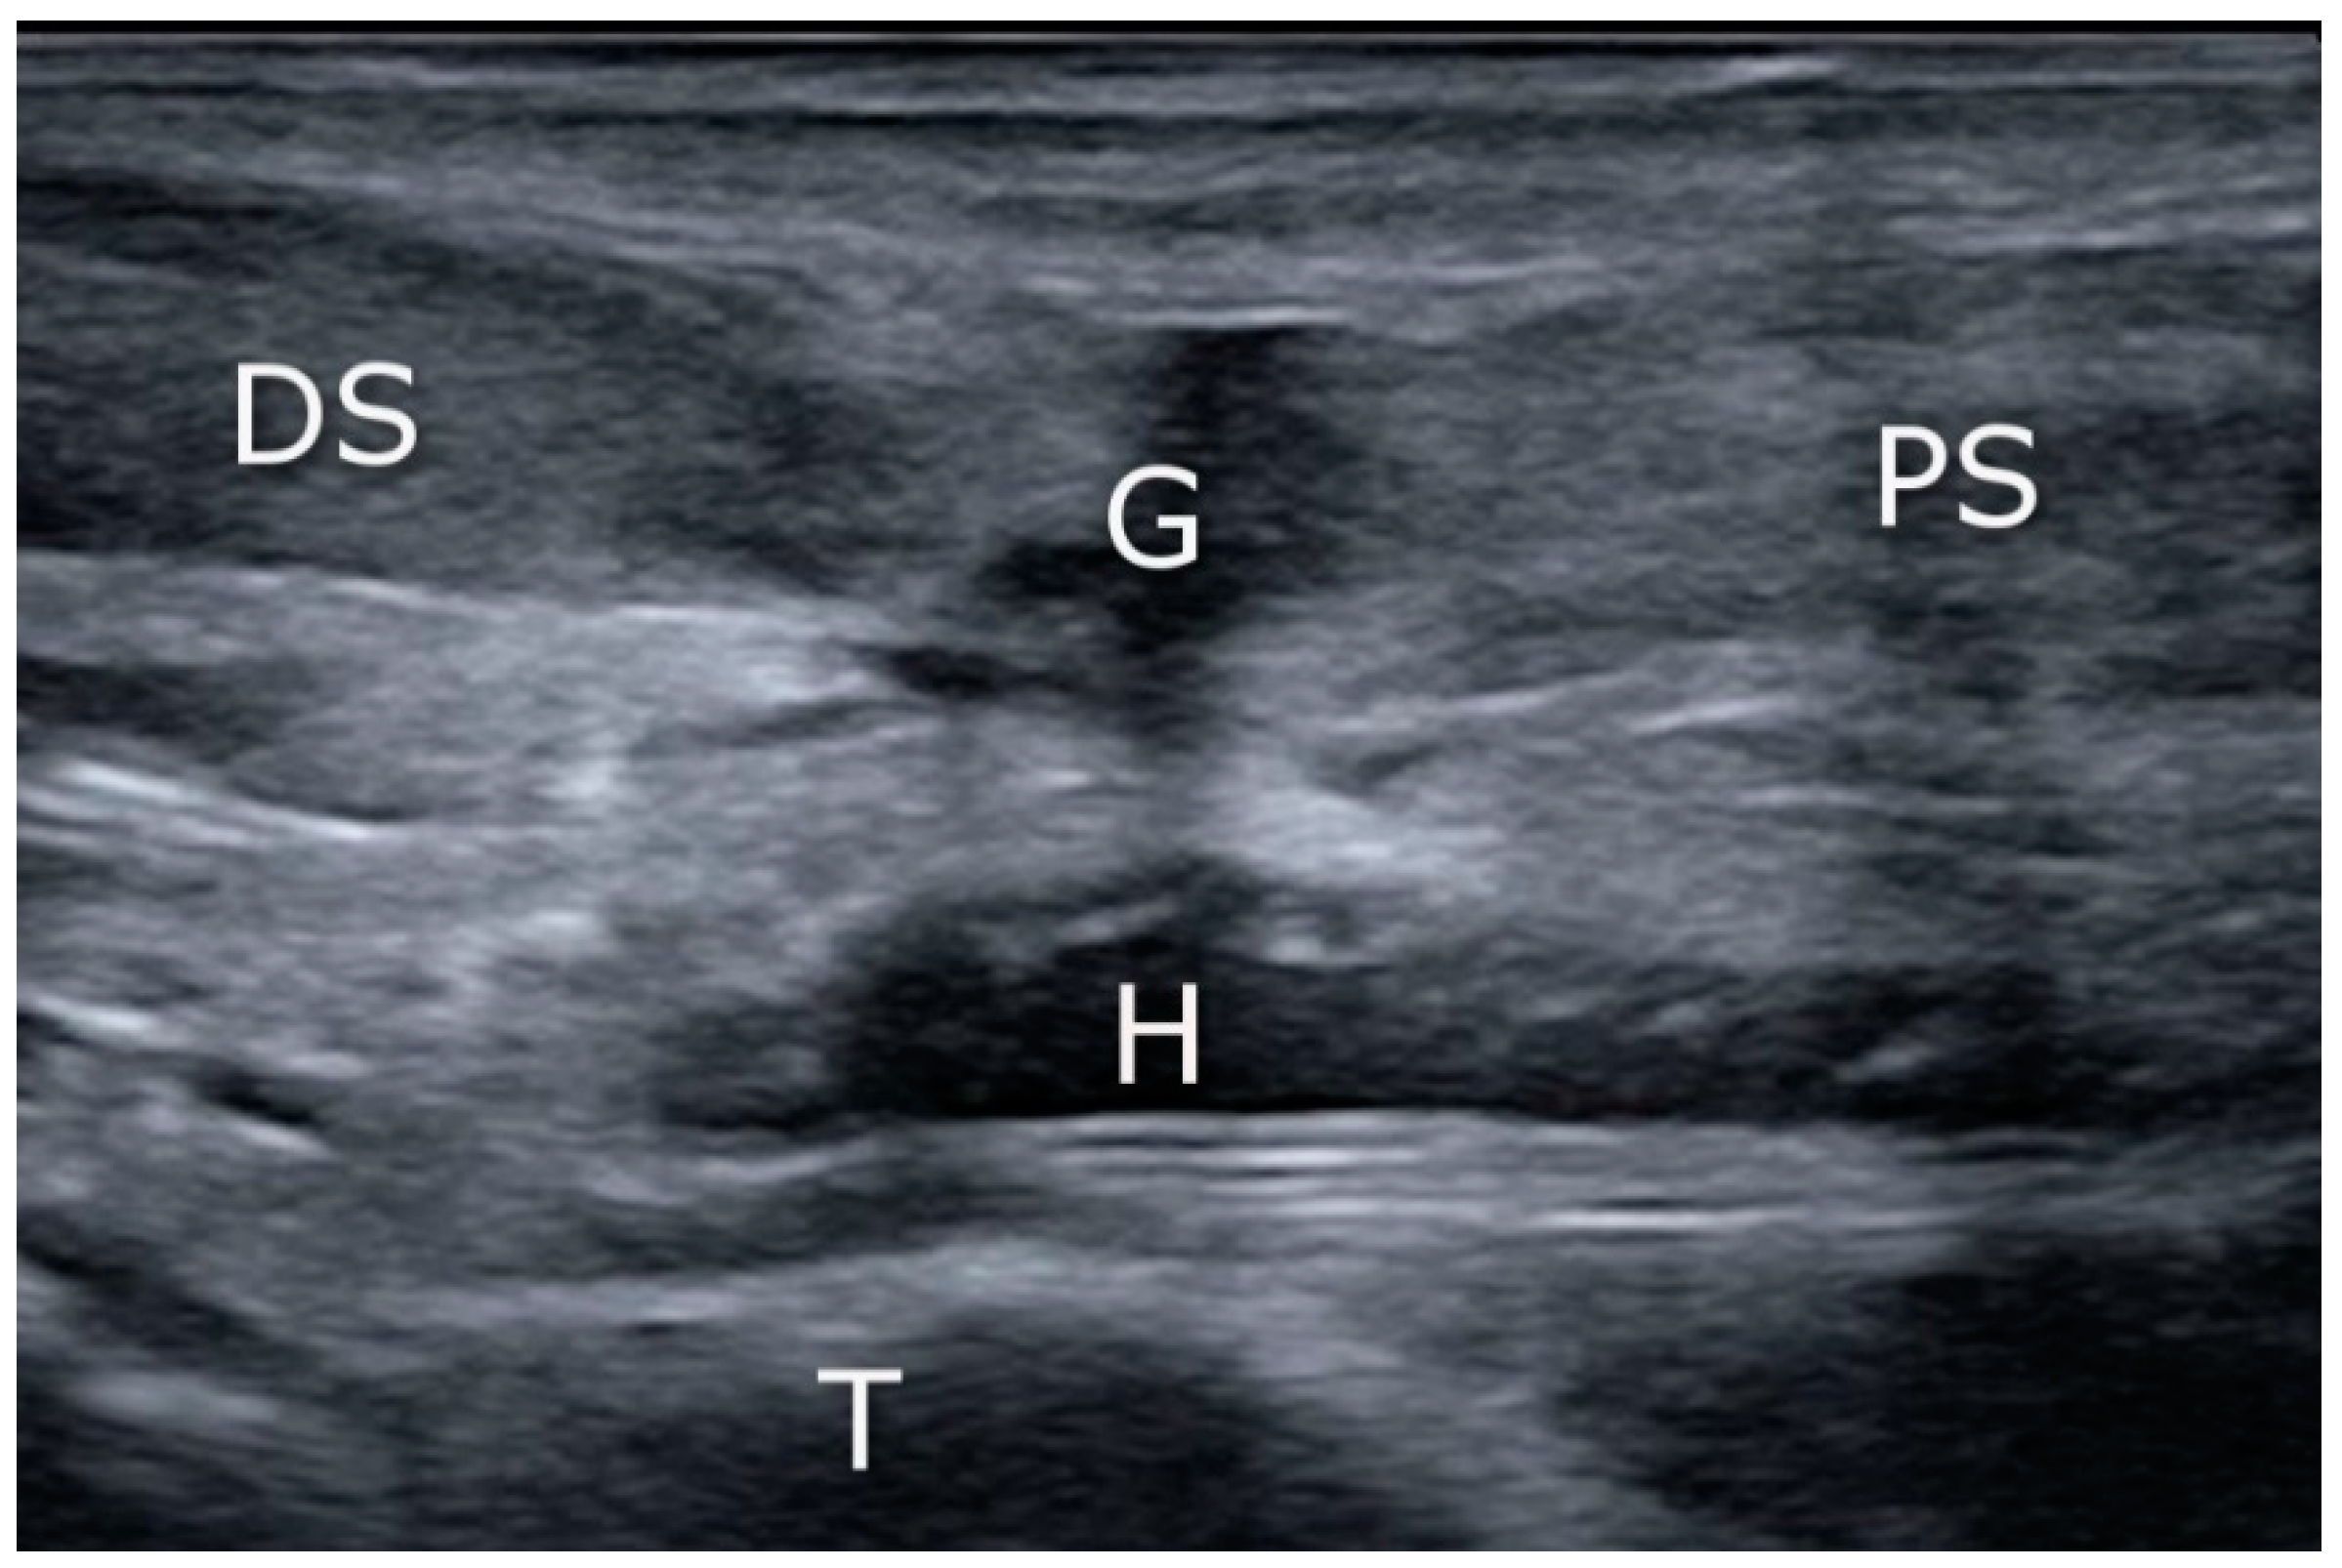

The operative procedure was performed by two surgeons with considerable experience in minimally invasive orthopedic surgery and musculoskeletal ultrasound. The surgical procedure was performed under regional or general anesthesia with a calf tourniquet. The patient was positioned prone on the operating table. The skin was prepared, and the sterile drape was used in the standard fashion. In the US-assisted group, the first step was to visualize the site of the rupture by means of ultrasound (linear probe 10–12 Mhz) (Figure 1). In the non-guided group, the rupture site was located by palpation. A transverse incision was made over the Achilles tendon defect using a surgical blade (size 11), and the tissue was spread with forceps to expose the paratenon (Figure 2).

Figure 1.

Achilles tendon tear: the sonographic appearance of acute Achilles tendon tear in the sagittal plane. G: gap (tendon lesion); H: hematoma; PS: proximal stump; DS: distal stump; T: tibia.